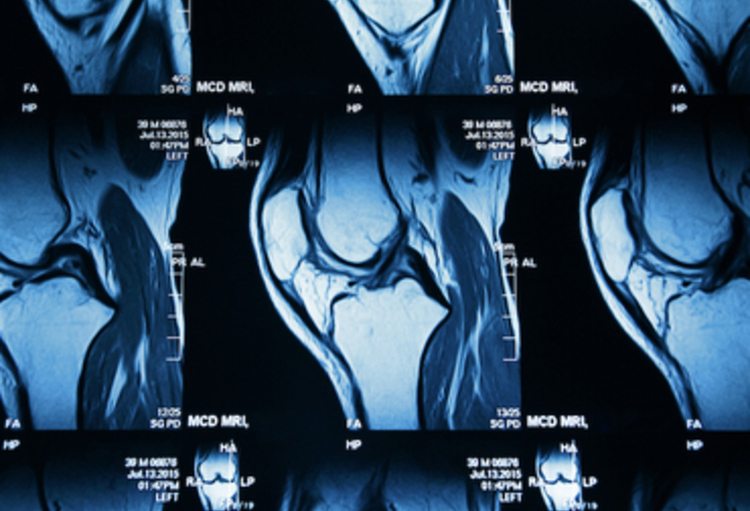

Traditionnellement, la détection d’une sacro-iliite active joue un rôle crucial dans le diagnostic précoce et le suivi d’affections inflammatoires telles que la spondylarthrite. Mais l’évaluation des images IRM de l’articulation sacro-iliaque (SI) constitue un défi en raison de la variabilité des lésions inflammatoires et de l’expertise requise pour une interprétation précise.

Dans cette nouvelle étude, des chercheurs du VIB-UGent et de l'UZ Gent ont mis au point un système de vision par ordinateur pour automatiser l'ensemble du processus, depuis la détection de l’articulation SI et la segmentation des régions jusqu’à la prédiction de l’œdème médullaire.